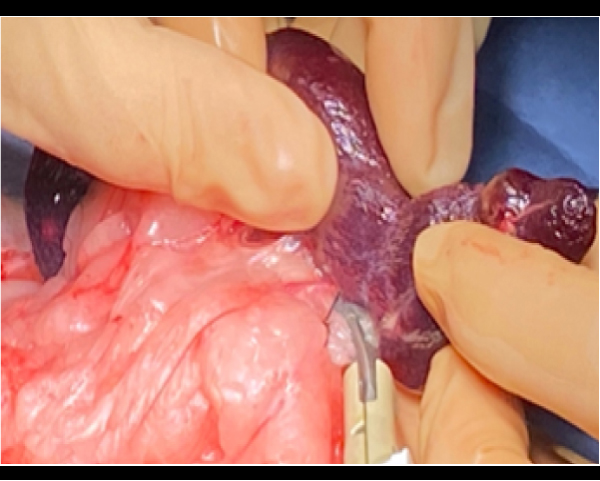

脾臓摘出を同日実施